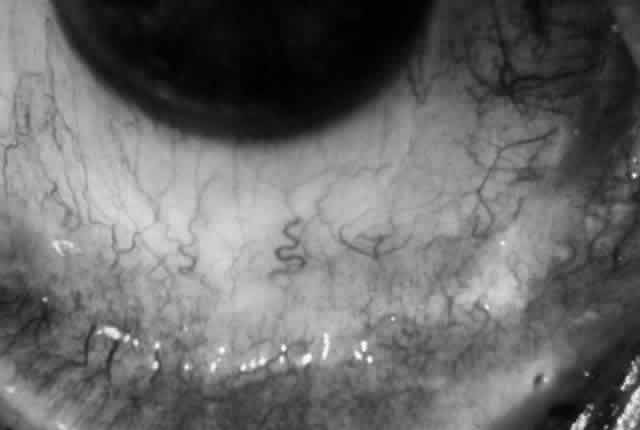

Clinically, the ocular disease in cicatricial pemphigoid (OCP) may present unilaterally in the form of a chronic, recurrent catarrhal conjunctivitis, but it eventually becomes bilateral. Subepithelial fibrosis is characteristic of stage 1 of OCP (Fig. 7). Stage 2 shows fornix foreshortening (Fig. 8), and symblepharon formation is the hallmark of stage 3 (Fig. 9). Stage 4, end-stage disease, is characterized by ankyloblepharon and surface keratinization (Fig. 10). Obstruction of the lacrimal ductules and meibomian gland ducts eventually produces an unstable tear film and progressive sicca syndrome, but it is to be emphasized that OCP is not a dry-eye syndrome until late in the disease course.20 Trichiasis and entropion occur because of the subepithelial fibrosis, with eventual keratopathy, corneal neovascularization, and corneal ulceration and scarring.20

Fig. 9. Stage 3 of an eye affected by cicatricial pemphigoid. The conjunctival “shrinkage” continued and a frank symblepharon developed.

Fig. 10. Stage 4 cicatricial pemphigoid. Progressive shrinkage of the conjunctiva resulted in extreme trichiasis and distichiasis and keratopathy, with compromise of meibomian ductules and lacrimal ductules and the production of a totally dry eye.